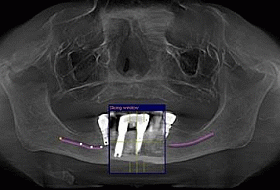

This CT scan shows the status before the treatment – existing 4 Branemark implants in the lower front jaw (this treatment was done by another clinic some years prior to this treatment) and absence of teeth in the lower back right and left. Upper jaw bone has deteriorated due to absence of all teeth and years of wearing full denture.

In order to make it possible to place implants in the upper jaw, sinus lifts (right and left) were required as well as cortical bone transplant from the patient’s hip to the front area of the upper jaw bone. Patient’s denture was also adjusted following bone augmentation, which required 6 months healing period before implants can be placed.